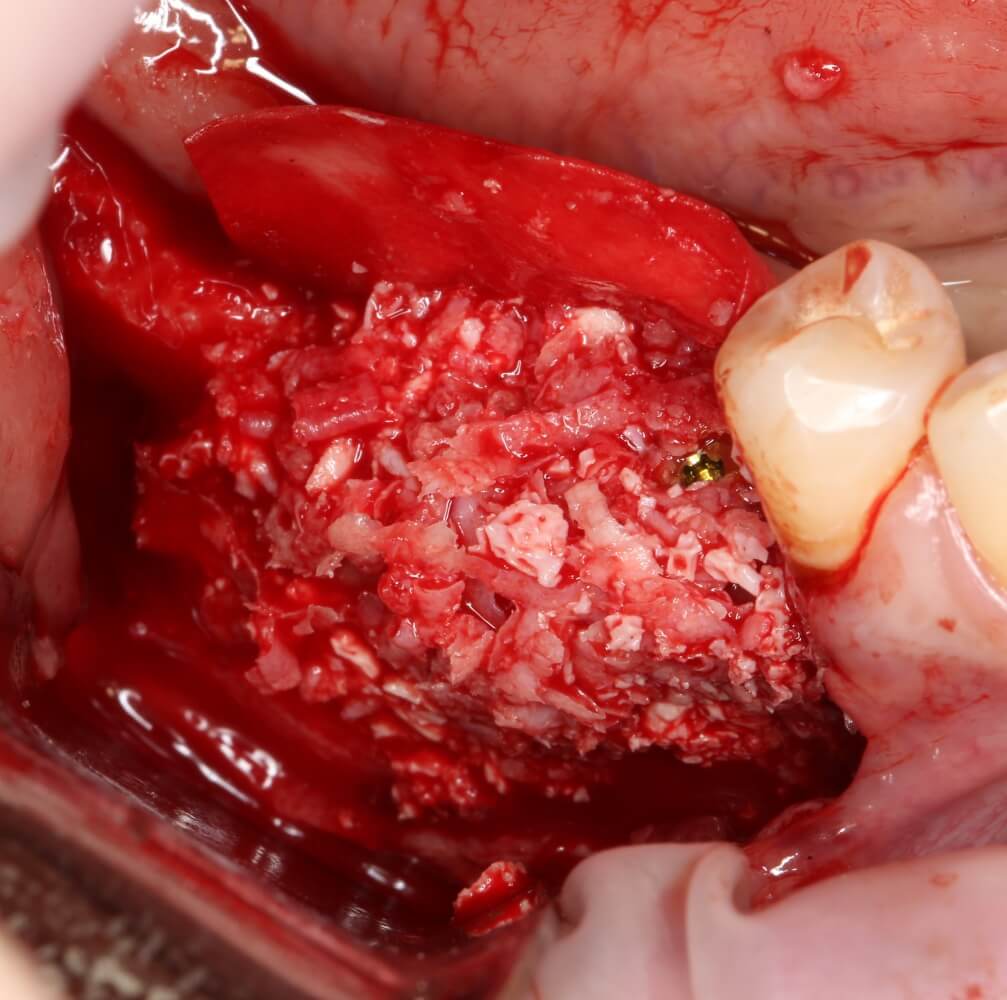

Возвращаемся к основной операционной области. Еще раз посмотрим на альвеолярный гребень, поофигеваем от его ширины и моих грандиозных планов:

Я зафиксировал костный блок практически без адаптации на несколько винтов. Обрати внимание, что винты находятся в зоне, где не планируется установка имплантатов. Фиксация должна быть надежной, поскольку мне еще предстояла подготовка лунок для имплантатов. Трех винтов для этого вполне достаточно.

Дальнейшая адаптация костного блока свелась к сглаживанию острых краев. После чего я приступил к подготовке лунок и установке имплантатов.

Глянем на то, что получилось:

Осталось адаптировать костный блок (убрать острые края), проверить его фиксацию и, при необходимости, добавить винты. Десятисекундное дело.